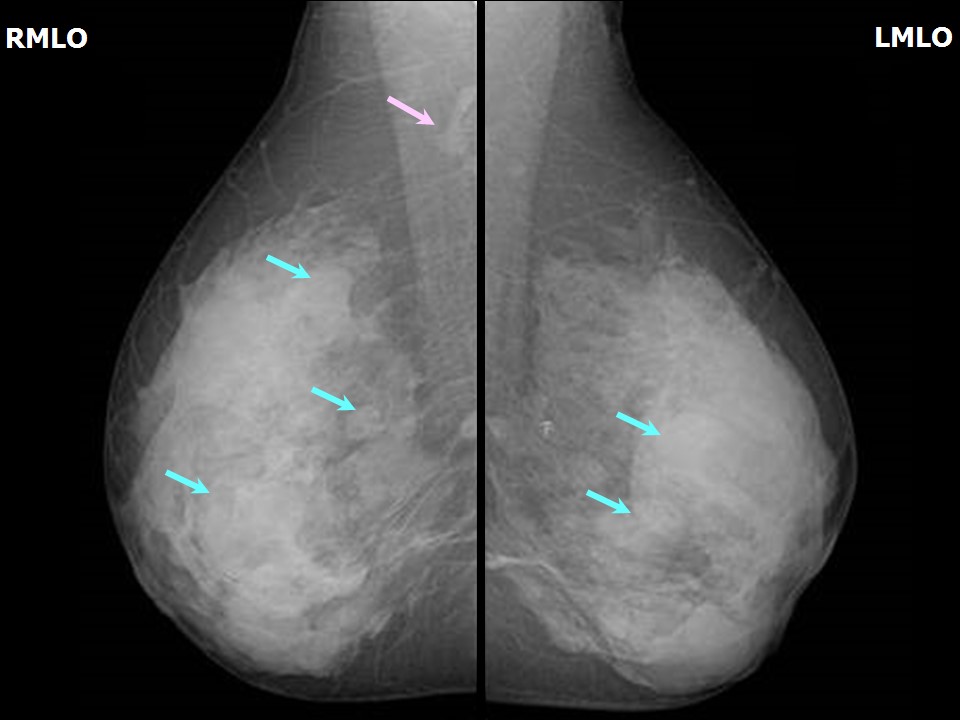

Феномен гипердиагностики в маммографии: примеры и иллюстрации

Раздел: Образы вокруг